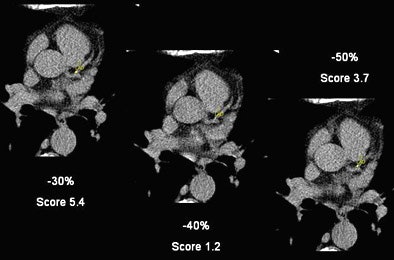

![]() |

| A small calcification within the LAD shows the variability of calcium scores based on the reconstruction interval. The -30% reconstruction interval yields a calcium score of 5.4, a -40% reconstruction drops the score to 1.208, and at -50% reconstruction it is 3.7. |